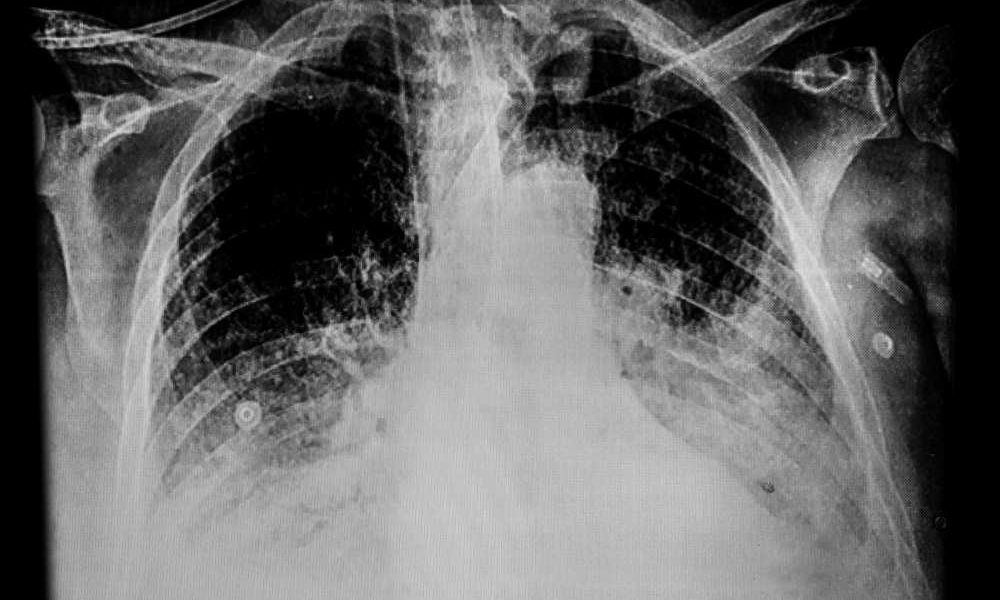

Nową terapię ratującą życie pacjentów hospitalizowanych z powodu Covid-19 opracowali brytyjscy naukowcy. Ma ona zastosowanie u osób, które nie są w stanie w naturalny sposób wytworzyć...

Naukowcy zidentyfikowali mechanizmy, poprzez które COVID-19 może prowadzić do otępienia podobnego do choroby Alzheimera. Okazuje się, że SARS-CoV-2 ma kilka wspólnych szlaków z mechanizmami powodującymi zapalenie...